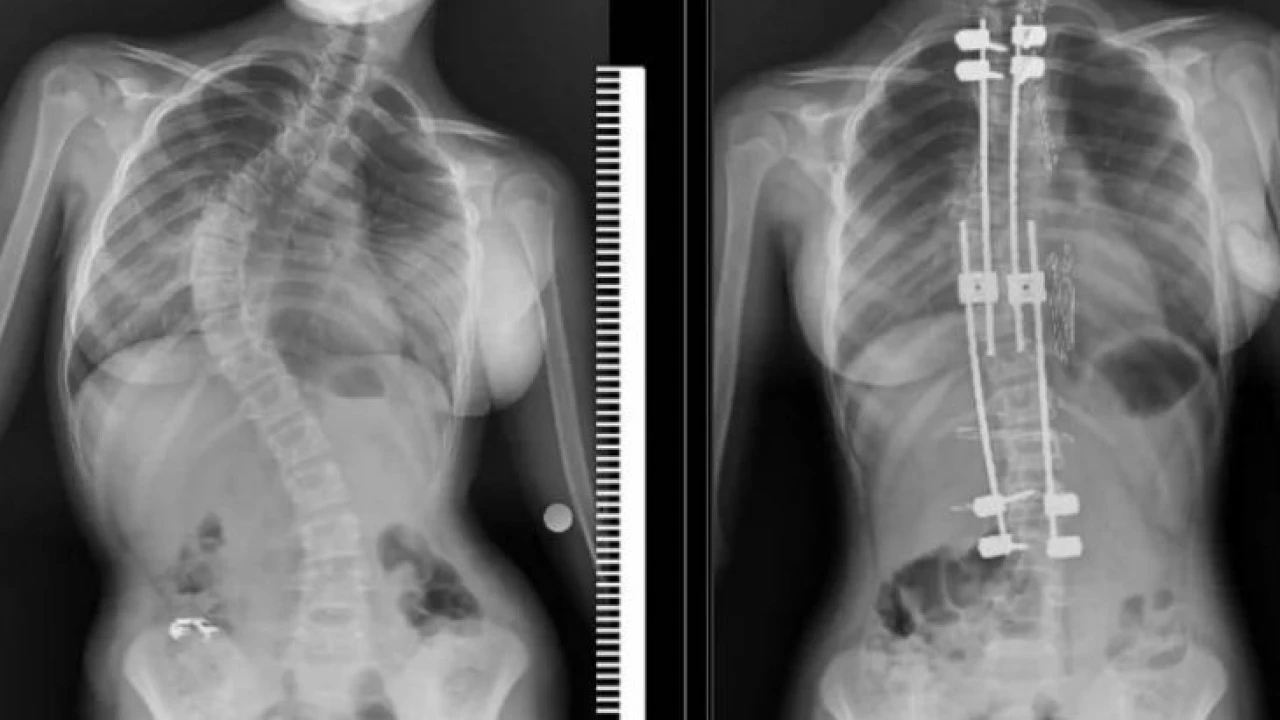

Samsun’un Bafra ilçesinde yaşayan 10 yaşındaki Zümra Demircioğlu bel ve sırt bölgesinde aşırı ağrı ve günlük aktivitelerini yapmakta zorlanma şikayetleri nedenleriyle Samsun Eğitim ve Araştırma Hastanesi’ne başvurdu. Burada çekilen röntgen ve yapılan tetkikler sonucunda 75 derece omurga eğriliği tespit edilen minik Zümra için ameliyat kararı verildi. Büyüme koruyucu sisteminin uygulandığı ameliyatta minik Zümra’nın omurgası düzeltildi. Özel hastanelerde ortalama 300 ile 500 bin TL arasında yapıldığı öğrenilen bu ameliyat artık Samsun Eğitim ve Araştırma Hastanesi’nde ücretsiz olarak gerçekleştiriliyor.

Ameliyat hakkında bilgi veren Dr. Ömer Bozduman, "Bu gibi durumlarda uzayan rot dediğimiz bir sistem uyguluyoruz. Bunun nedeni çocukları yaşı küçük olduğu için füzyon dediğimiz kaynatma ameliyatı yaparsak akciğerlerinde yetersiz gelişme, göğüs kafeslerinde yetersiz gelişme ve kanallarında yetersiz gelişme oluşabileceği için büyüme koruyucu cerrahi yapıyoruz. Büyüme koruyucu cerrahinin diğer füzyon cerrahisinden alternatifi şudur: Düzenli aralıklarla düzeltme yapıyoruz. Çocuk büyüdükçe biz de bu sistem anestezi altında ya da anestezisiz olarak uzatarak çocuğun yeterli omurga büyüklüğüne ulaştıktan sonra yeterli kalıcı ameliyatı gerçekleştiriyoruz. Anestezi hocamız Doç. Dr. Serkan Turgal yardımı ile bu ameliyatı başarıyla gerçekleştirdik. 10 yaşındaki hastamıza büyüme koruyucu sistemi yerleştirdik. Düzenli aralıklarla uzatmalarını yapacağız. Nihai ameliyatını omurgası büyüdükten sonra gerçekleştireceğiz. Eğitim ve Araştırma Hastanesi olarak bir ilki gerçekleştirdik. Hastamız gayet iyidir. Birinci günün kalkıp yürüdü. Dördün gün sonra taburcu ettik. Herhangi bir nörolojik veya başka bir sorunla karşılaşmadık. İhtiyacı olan tüm hastalarımıza Samsun Eğitim ve Araştırma Hastanesi olarak devletimizin imkanlarıyla bu hizmeti ücretsiz olarak veriyoruz. Aileler bu semptomlar hakkında dikkatli olmalıdır. En ufak şüphede polikliniklerimize bekliyoruz. Bizler yardımcı olacağız" diye konuştu.